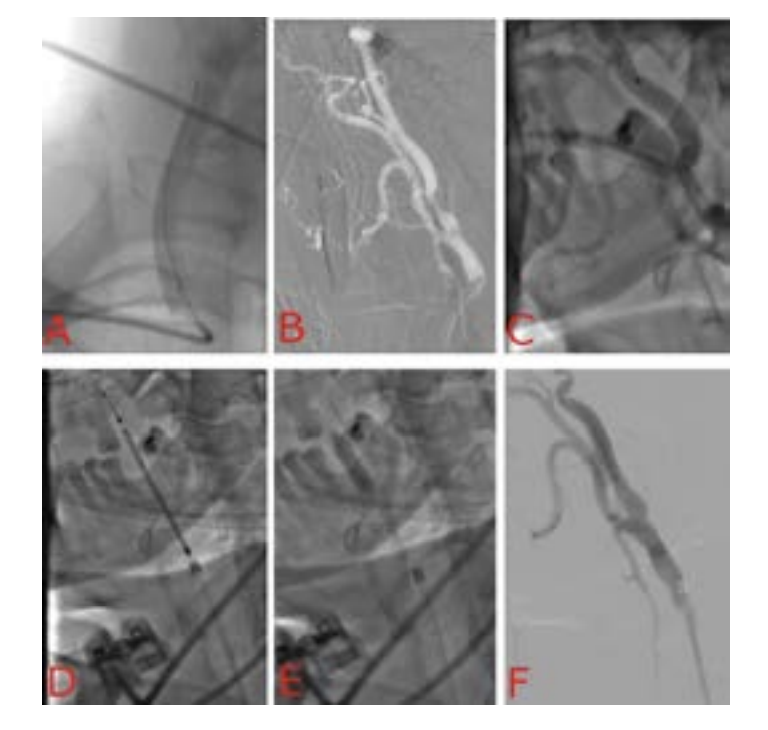

The patient’s case was discussed at our cardio team meeting and percutaneous carotid artery stenting was advised given the high cardiovascular risk for carotid artery endarterectomy. Right radial access was chosen for the procedure with a standard 6F sheath. An XB 3.5 guide catheter was advanced to the aortic arch. The guidewire was withdrawn to allow the catheter to bend on itself and with slight rotation we directed the catheter tip towards the brachiocephalic trunk.

A stiff Terumo 300 cm wire was advanced towards the common carotid artery (CCA), under road map guidance and the wire was advanced to the distal portion of the external carotid artery. The guide catheter and the sheath were withdrawn and exchanged for a 6F 90cm long sheath and advanced to the common carotid artery.

A Runthrough extra floppy wire was advanced to the distal internal carotid artery, and the spider FX filter wire was secured 3 centimeters distal to the ICA lesion. A Protege Rx carotid stent was then deployed followed by post dilation with a 5.0 x 20 mm balloon (Figure 1). The intraoperative course was smooth and then the patient was transferred to the ICU.

We reviewed the angiograms again and we discovered a small perforation at the takeoff of a very small branch of the external carotid artery (Figure 2). We reviewed the literature for recommendations and we found similar cases but at the ECA itself that required coiling and embolization.4